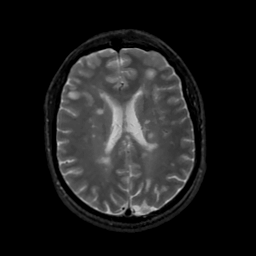

MR Study #13, May 19, 1991 -- Slice #31